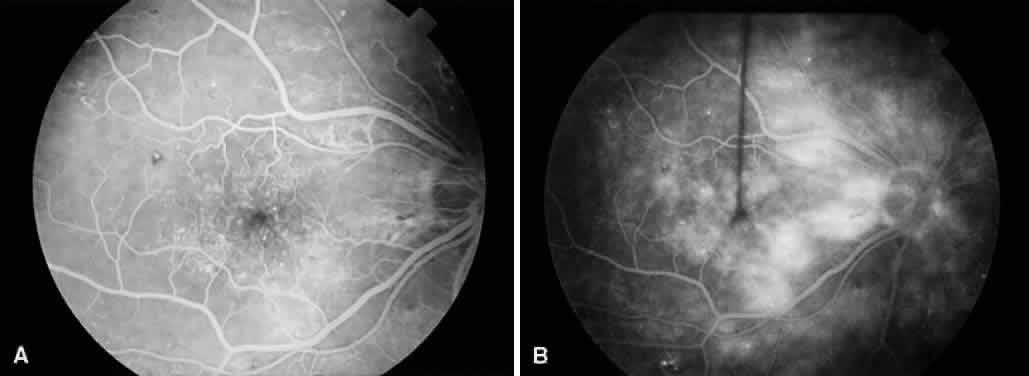

Fig. 5. A. Preoperative fundus photograph of an eye with combined traction-rhegmatogenous retinal detachment from severe proliferative diabetic retinopathy. B. Postoperative fundus photograph of the same eye after vitrectomy, membrane dissection (using delamination technique), and endolaser photocoagulation.

Vitreous traction and contraction of proliferative tissue can produce retinal tears, leading to combined traction-rhegmatogenous detachments. Unlike purely tractional detachments, extramacular rhegmatogenous detachments frequently progress to involve the macula, leading to rapid and severe visual loss. Thus, surgical repair is indicated in combined detachments, whether or not the macula is involved. Often, the retinal breaks are located posterior to the equator, adjacent to areas of fibrovascular proliferation that are under severe vitreoretinal traction. Therefore, this condition is difficult to treat by conventional scleral buckling methods, whereas vitrectomy (with or without scleral buckling) is effective in treating this condition (Fig. 5). Intraocular long-acting gas tamponade is required to treat these detachments. Combined traction-rhegmatogenous detachments have a lower success rate than pure tractional detachments or nonclearing vitreous hemorrhage. In an analysis of 172 eyes that underwent vitrectomy for combined traction-rhegmatogenous diabetic retinal detachment, 48% had an improved visual acuity on final examination.21 A final visual acuity of 20/100 or better was achieved in only 25% of eyes, and a final visual acuity of 5/200 was achieved in 56%. Visual loss progressed to no light perception in 23% (compared with 19% for macular traction detachment and 6% for nonclearing vitreous hemorrhage). Preoperative factors associated with a favorable visual prognosis included visual acuity of 5/200 or better, absence of iris neovascularization, and absence of retinal detachment involving the macula. The only intraoperative factor found to be associated with a favorable visual prognosis was the absence of iatrogenic retinal breaks.